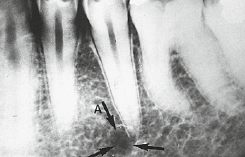

53. What is showing by arrow?

Inferior Alveolar Canal appears as a dark linear shadow with thin radiopaque superior and inferior borders cast by the lamella of bone that bounds the canal